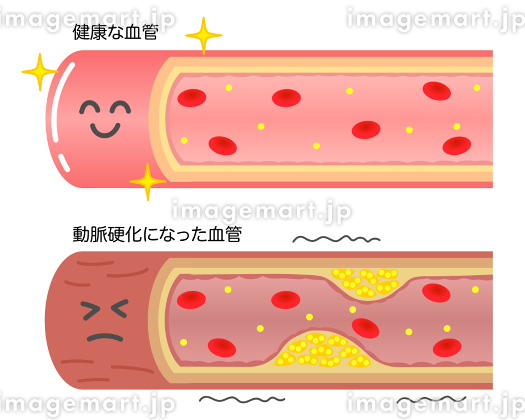

血栓症」のイラスト素材・ベクター画像 - イメージマートimagemart。

血栓症」のイラスト素材・ベクター画像 - イメージマートimagemart。

正常な血管と血栓ができた血管 イラスト素材5358451- フォトライブラリ。

動脈硬化、血栓形成。ベクトル医療イラスト。内部の臓器、血栓症、血管内皮のイラスト素材・ベクター Image 61855962。

血栓ができている血管 イラスト素材6665451- フォトライブラリ。